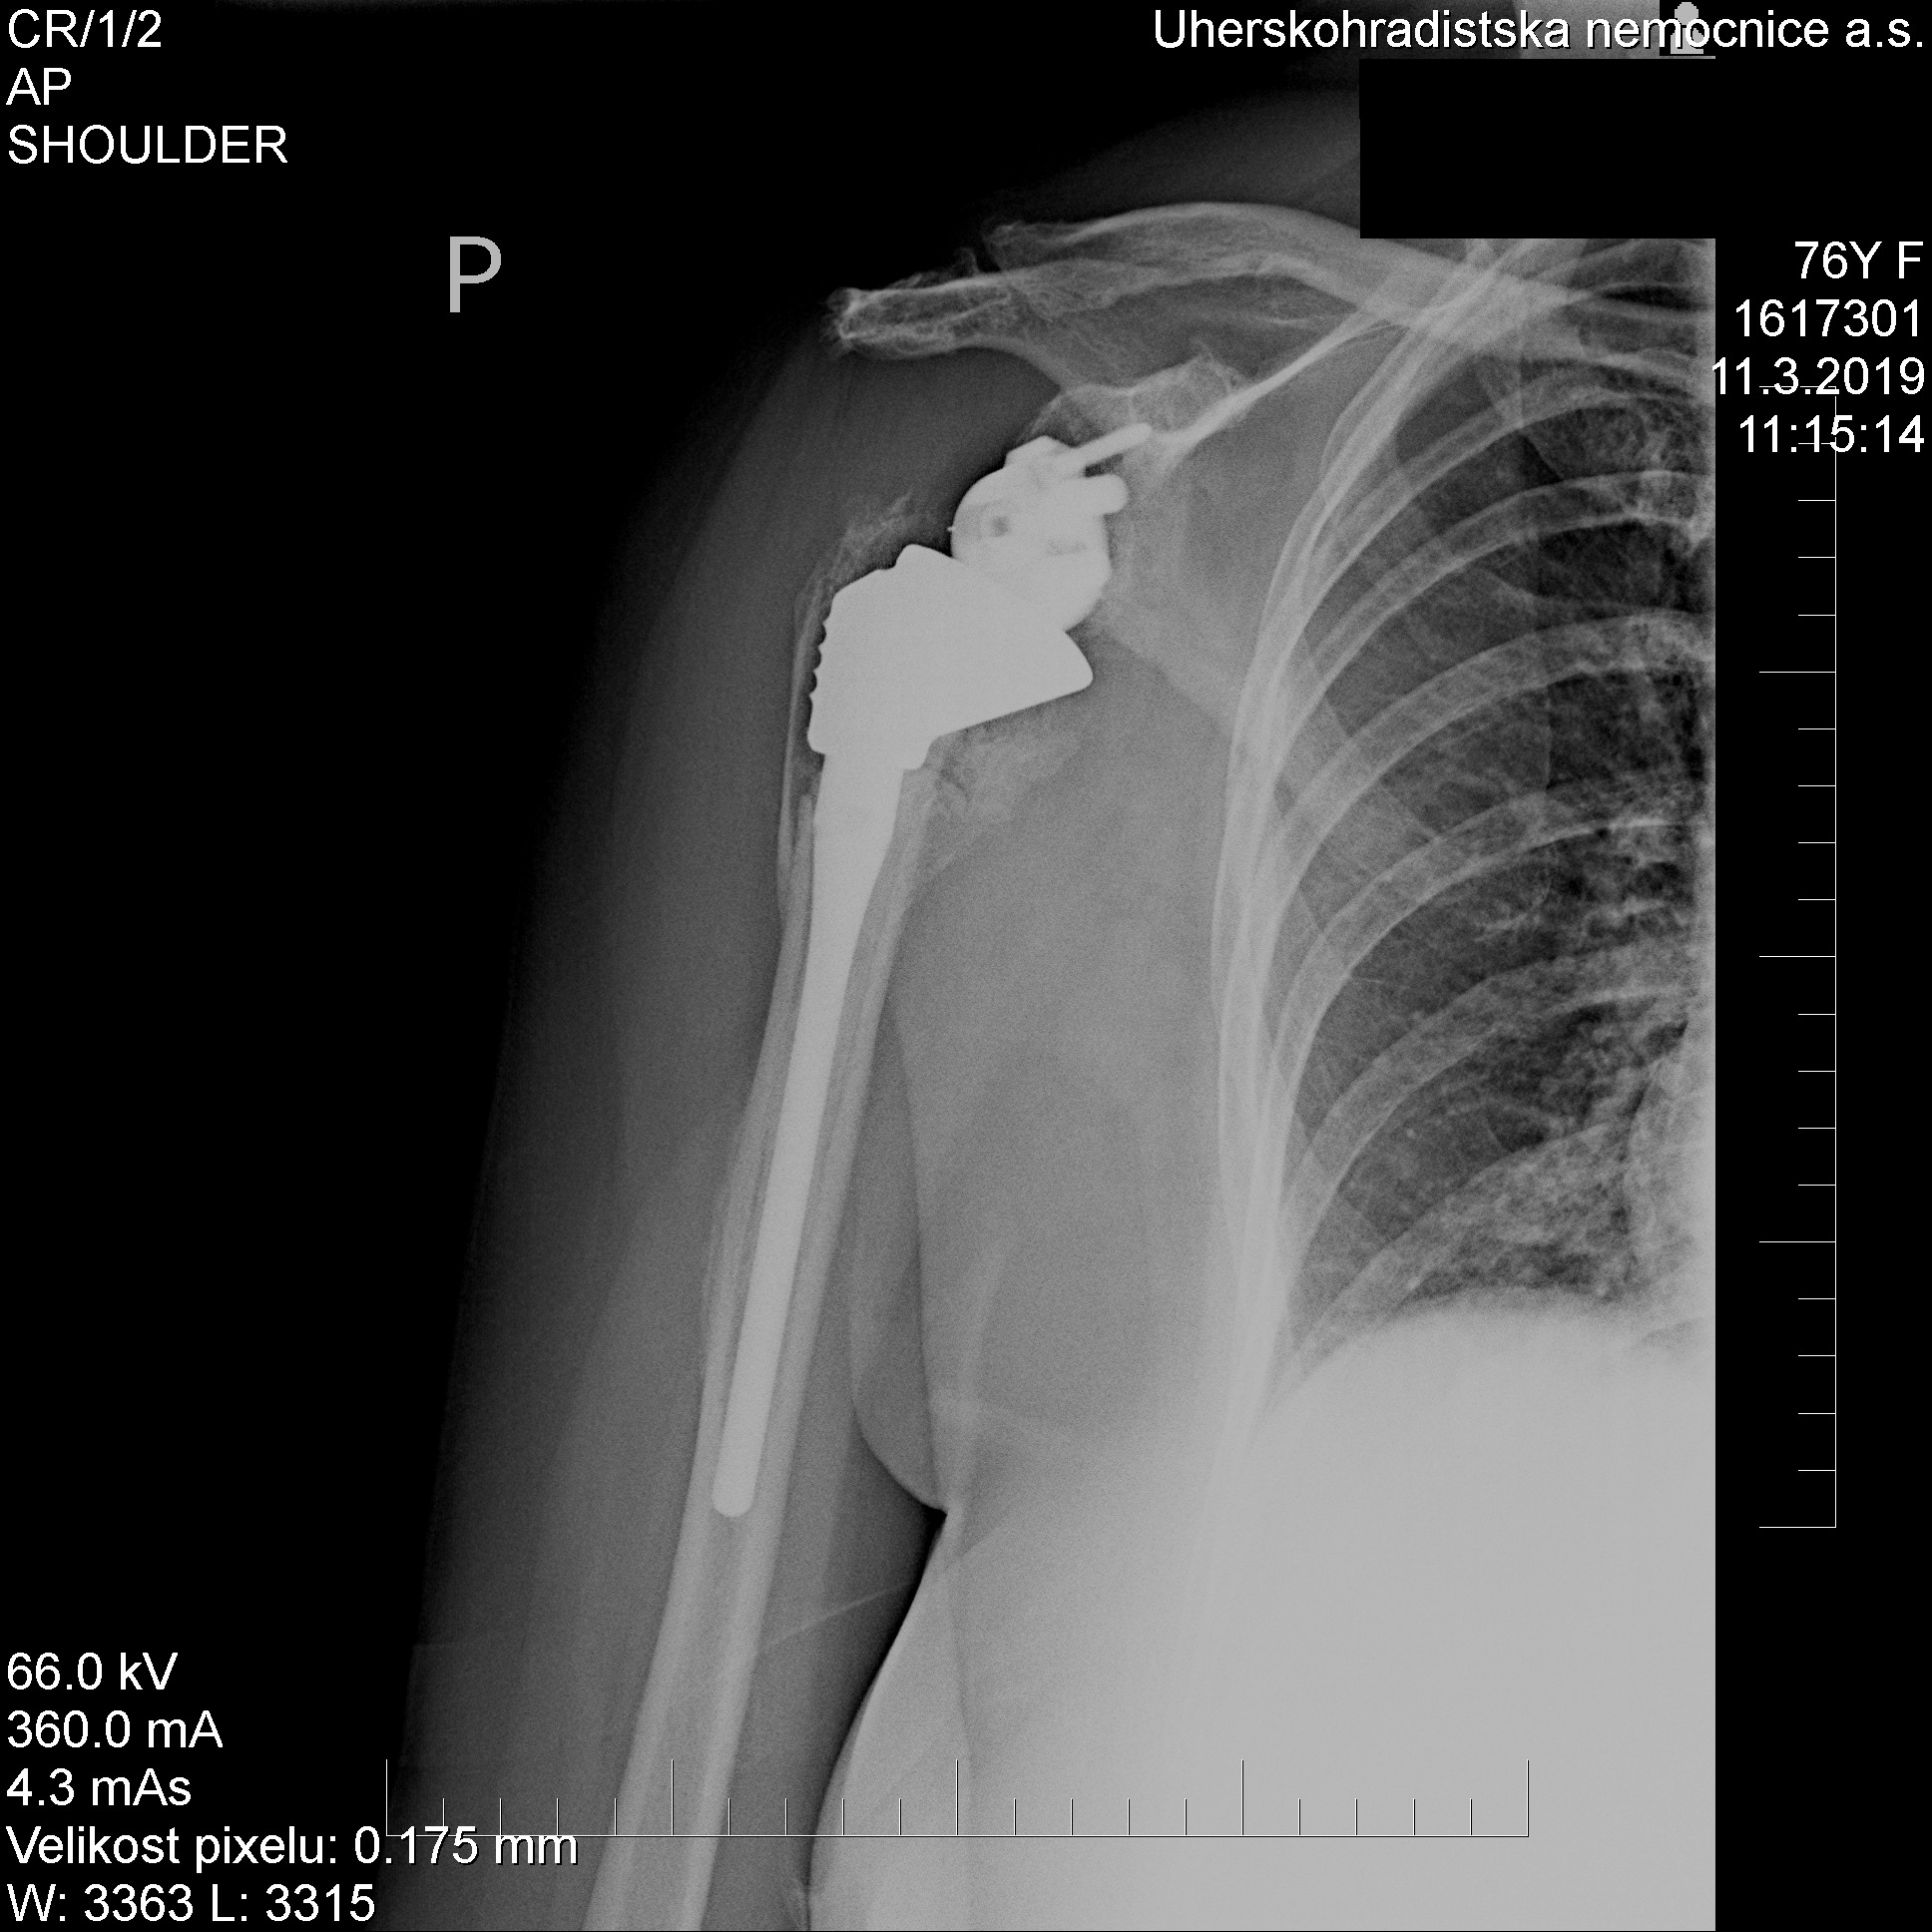

„Náhrada ramenního kloubu má svá specifika. Atypická je například v tom, že se původní hlavice pažní kosti mění v jamku, přičemž hlavice endoprotézy se kotví do lopatky. Právě tato záměna, tedy reverzní náhrada kloubu, pak umožňuje plnou hybnost a stabilitu ramene. „Kotvení náhrady právě do lopatky je navíc dost nesnadné a limitované, jedná se totiž o kost docela tenkou a subtilní,“ popisuje princip náhrady ramenního kloubu primář Ortopedického oddělení Uherskohradišťské nemocnice Martin Skládal.